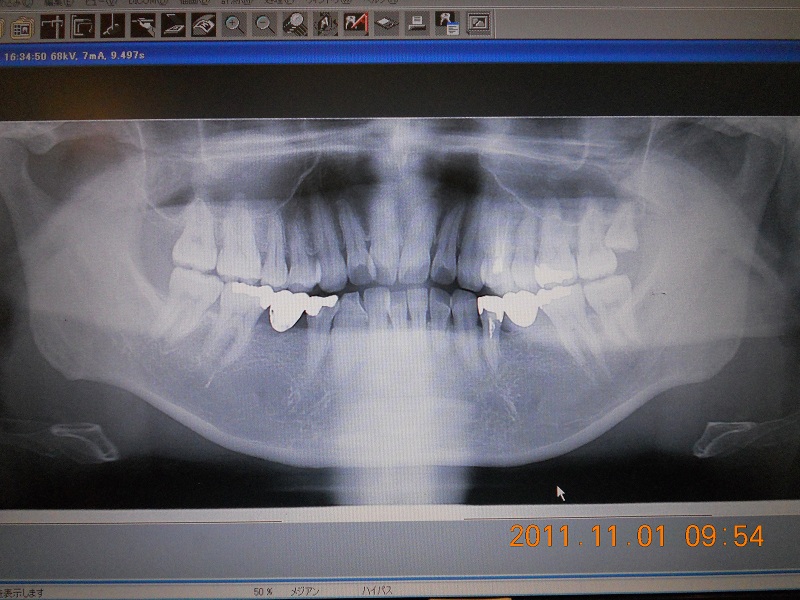

虫歯は小さいものであれば、悪い部分を削り、詰め物や被せもので補うだけで治療が終わります。しかし、進行した虫歯は、歯の内部にある神経にまで炎症を起こし、強い痛みを伴うだけでなく、さらに進行すると歯の根の奥にまで炎症が波及し、歯を支えている骨にまで炎症を起こします。このような場合は一定期間の継続的な治療が必要です。

歯周炎は、口の中で磨きにくい部分にたまった汚れ(プラーク、歯石)が原因で、歯を支えている歯ぐきや骨に炎症を起こし、進行すると歯がぐらついて食事などに違和感や痛みを感じるようになります。汚れをきれいに取り除くことで炎症を改善します。進行状況により治療期間は異なりますが、治療は一度きりでなく、定期的なケアが必要です。

安心して治療を受けていただけるよう、事前に画像検査なども参考に丁寧にご説明いたします。